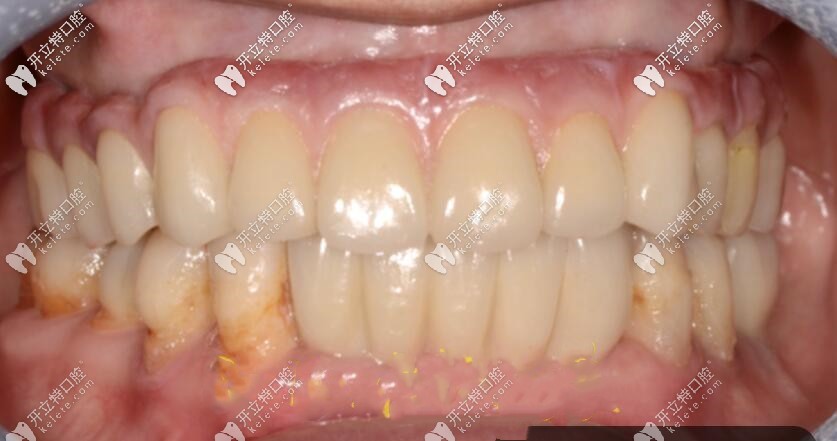

半口即刻負(fù)重種植牙效果圖來(lái)咯,讓大家親自感受靠譜不

人工種植牙半口種植牙即刻負(fù)重發(fā)布時(shí)間: 2025-02-12

總有人好奇半口種植牙的效果究竟好不好,今天以實(shí)際案例告訴大家,好不好,大家自己感覺(jué)一下吧!